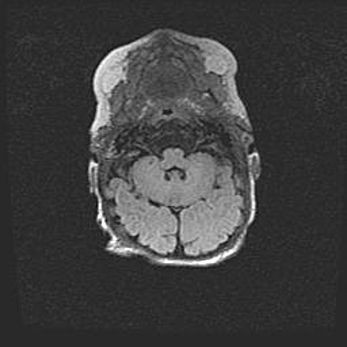

Множественные кисты обоих полушарий головного мозга, наибольшая из них в правой затылочной области. Ассиметричная атрофическая гидроцефалия.

Возраст: 7 месяцев

Вес: 5660 г

Пол: мужской

Окружность головы: 41,5 см

Срок гестации: 28-29 недель

Кисты головного мозга развиваются в результате многоочаговых некрозов вещества мозга и возникают вследствие перенесенной перинатальной инфекции, менингитов, энцефалитов, асфиксии, родовой травмы, расстройств мозгового кровообращения различного генеза. Образованию кист в веществе головного мозга плодов и новорожденных способствуют такие факторы, как высокое содержание в нем воды, недостаточная (или отсутствие) миелинизация и слабая астроглиальная реакция на повреждение.

Кисты могут сочетаться с гидроцефалией и другими поражениями головного мозга.